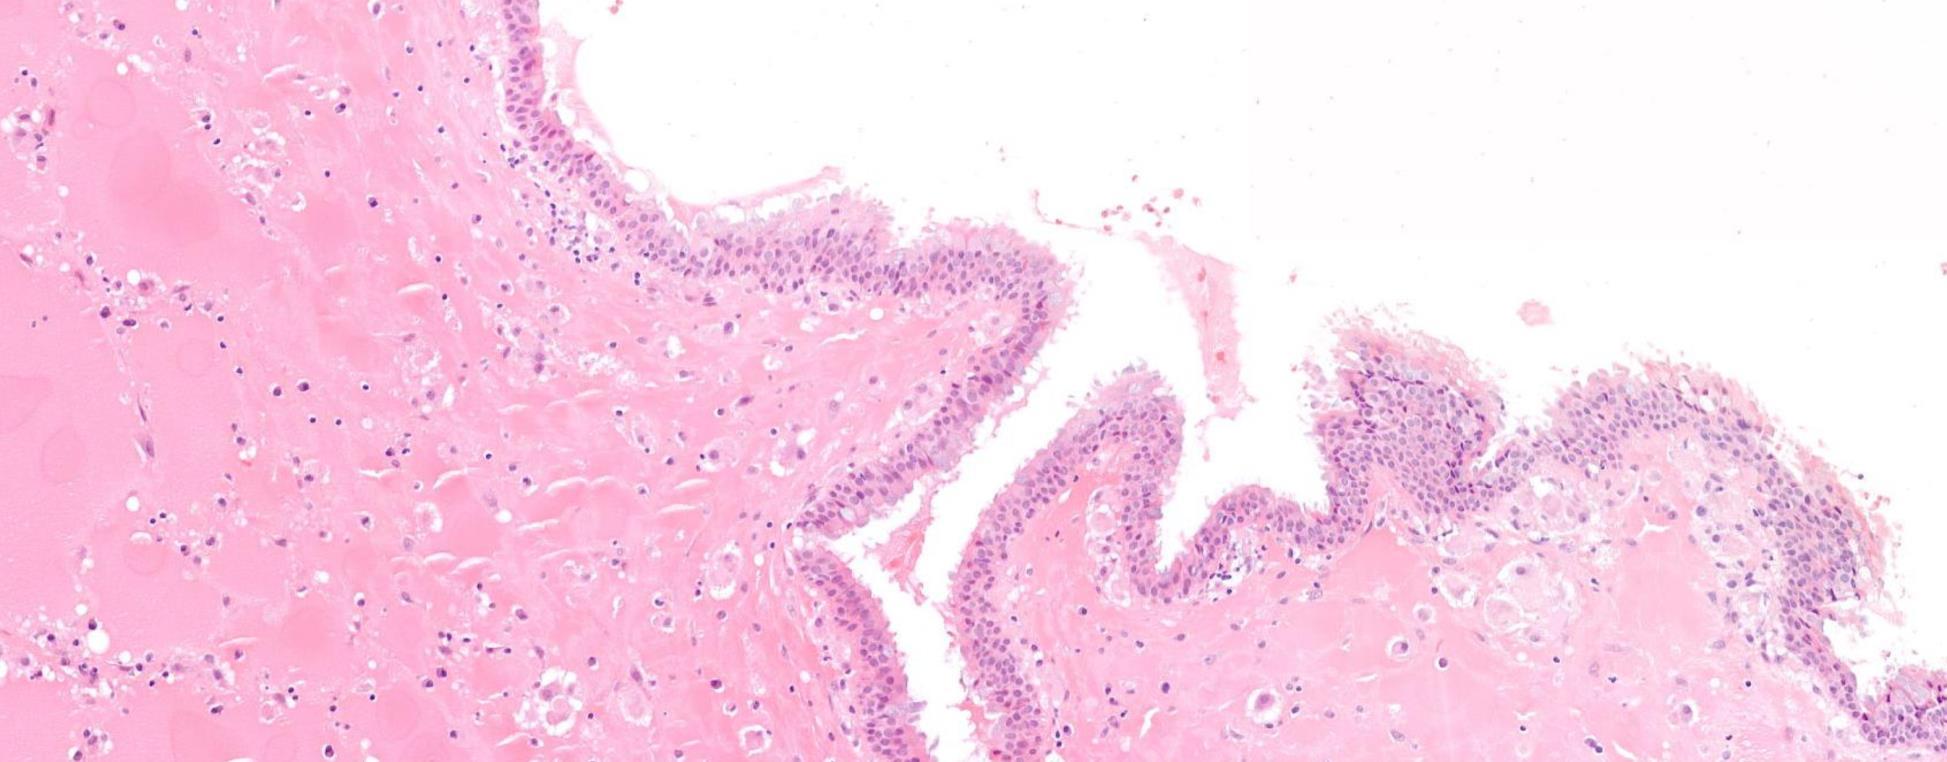

38-year-old Female, Cyst Associated With Unerupted Wisdom Tooth.

??

Case 9 Diagnosis

Odontogenic keratocyst

Salient points •Basal cell palisading •Corrugated parakeratosis •Focal inflammation –loss of above and “non-specific” features •Consistent loss of PTCH tumour suppressor gene- GorlinGoltz syndrome •Tendency for recurrence